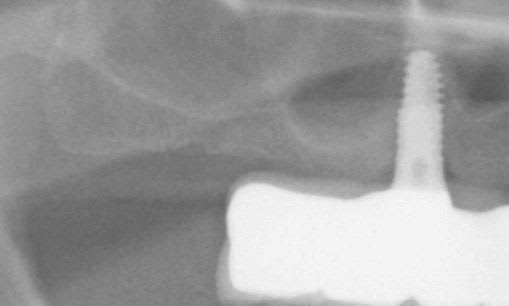

posit, le cas 3, avec les deux implants symphysaire, sans doute pour locator, a quand même l'air assez simple a main-levé .

J’en ais eu plusieurs pour 2 et 4 implants symphysaire, outre le fait de paralléliser ou avoir une angulation maitrisée la procédure permet un lambeau à minima et une localisation de l’artère sublinguale. Cette intervention peut être parfaitement réalisée à main levée. Lorsqu’ ‘il y a défaut de parallélisme des usures prématurées des Locator peuvent être constatées. Une chirurgie à main levée à un coût plus économique qu’une chirurgie guidée le choix peut se faire aussi en thermes de sécurité, confort, résultat,…

Pour calculer la précision post- opératoire il faut la comparer à une position déterminée pré-opératoirement, peut tu nous montrer la planification du cas que tu montre et au moins une OTP.

dans un post précédent je t'ai demandé des radios et la superposition de la planification et des radios post op montrait un delta de 15 à 20° de implants